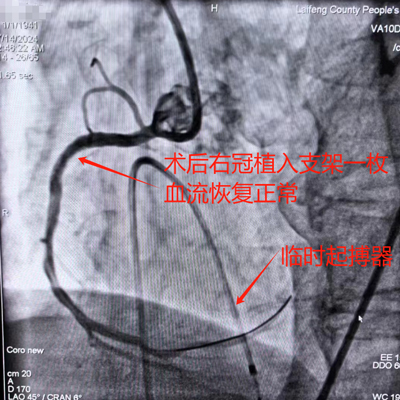

02:35 植入临时起搏器。

03:20 顺利结束手术。

该病例是在临时起搏器保护下顺利完成,也是来凤县人民医院胸痛中心救治急性心肌梗死患者的首个案例。